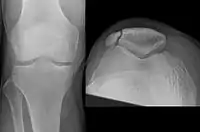

Osteochondral fracture of patella

Vertical patella fracture